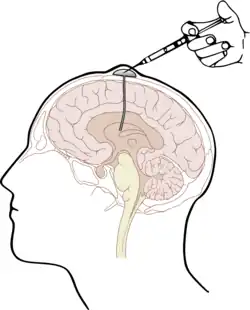

Die naheliegendste Form des Wirkstofftransportes in das ZNS unter Umgehung der Blut-Hirn-Schranke stellt die Injektion direkt in den Liquor cerebrospinalis (intrathekal) oder direkt in die Hirnventrikel (intraventrikulär)[11] dar. Der Wirkstoff wird dabei direkt in den Liquor injiziert. Angewendet wird dieses Verfahren beispielsweise als intrathekale Chemotherapie[12][13] unter anderem mit dem Folsäure-Antagonisten Methotrexat (MTX), mit Cytarabin (AraC) und Cortisol; speziell bei Patienten mit akuter lymphatischer Leukämie und aggressiven Lymphomen.[14] Die drei Wirkstoffe werden in der triple intrathecal chemotherapy zur Behandlung der Hirnhaut-Leukämie[15] zusammen in den Liquor appliziert.[16]

Die intrathekale Wirkstoffapplikation ist – verglichen mit der intravenösen (systemischen) Gabe von Wirkstoffen – deutlich aufwändiger und für viele Patienten auch unangenehmer. Darüber hinaus bestehen bei derartigen Darreichungsformen aufgrund der deutlich erhöhten Infektions- und Verletzungsgefahr besonders strenge Anforderungen an Hygiene und technische Fertigkeiten des Anwenders. Durch die Injektion von Wirkstoffen mit Depotwirkung (slow release) können die Behandlungsintervalle auf längere Zeiträume – beispielsweise 14-täglich – gestreckt werden.[16] Weniger aufwändig ist die Verwendung eines Ommaya-Reservoirs, das unter die Kopfhaut implantiert wird. Einen ähnlichen Ansatz bieten implantierbare Medikamentenpumpen.[17] Bei schweren Schmerzzuständen kann diese Methode beispielsweise für die Dosierung von Morphin gewählt werden.[18][19] Auch zur Behandlung von Spastiken, beispielsweise bei Multipler Sklerose mit Baclofen, kann der Wirkstoff über eine solche Pumpe intrathekal appliziert werden.[20][21][22] Die Methode wurde erstmals 1984 angewendet[23] und ist seitdem etabliert.[24][25]

Intrathekal applizierte Wirkstoffe werden meist speziell für diese Darreichungsform formuliert. Sie dürfen beispielsweise keine Bakterizide und eine Reihe anderer Hilfsstoffe enthalten, die in intravenös applizierten Medikamenten übliche Zusatzstoffe sind.[26]

Für einige wenige Erkrankungen ermöglicht die intrathekale beziehungsweise die intraventrikuläre Wirkstoffapplikation eine wirksame Therapie. Für die Behandlung von Hirntumoren sind diese beiden Methoden zur Umgehung der Blut-Hirn-Schranke allerdings nicht geeignet. Die Ursache hierfür liegt in der auf nur wenige Millimeter begrenzten Diffusion der Wirkstoffe in das Parenchym des Gehirns.[27][28][29]